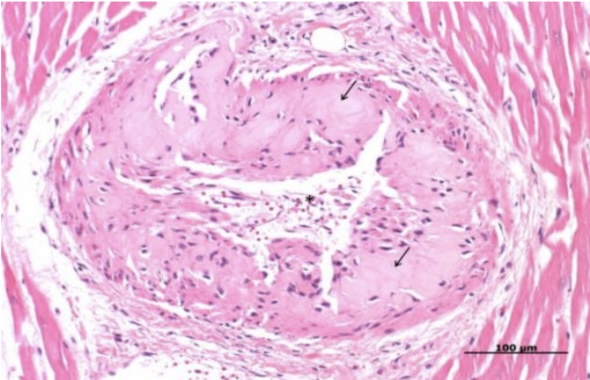

Hyaline degeneration

Hyalinization

Hyaline cast

Hyaline droplets